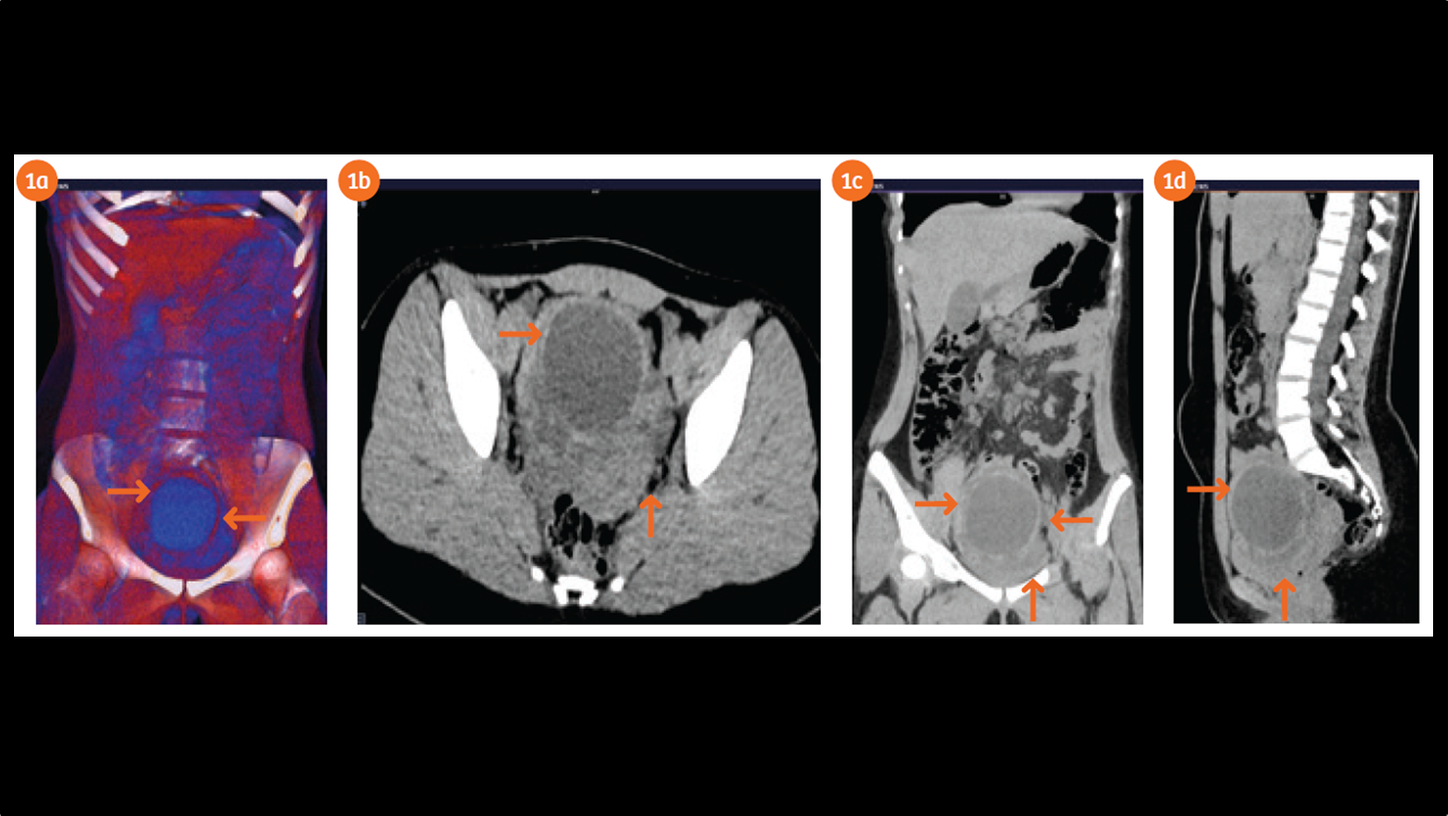

Whole abdomen low dose CT (ctdivol 160 mGy.cm and effective dose 2.4mSv) performed on SOMATOM Flash 256 slices machine showed a left-sided pelvic large cystic lesion measuring 7 x 8 cm in diameter (Figs. 1a–1d). There is no evidence of abnormal calcification within or in the wall of the cystic lesion. The lesion is causing significant mass effect on the urinary bladder and uterus. No renal stone is seen. No ureteric or pelvi-calyceal dilatation seen particularly in the left side. The rest of the structural anatomy includes kidneys, gall bladder, upper and lower abdominal areas appear to be normal.